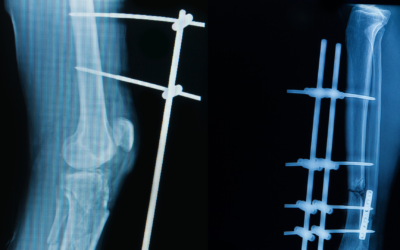

High-Quality Locking T-Fix T-Plate for Reliable Bone Stabilisation

Orthopedic surgery is a field where the margin for error is nearly non-existent. When a patient suffers a complex fracture, the primary goal of the surgeon is to restore anatomy and ensure the patient can return to their daily life as quickly as possible. Among the...